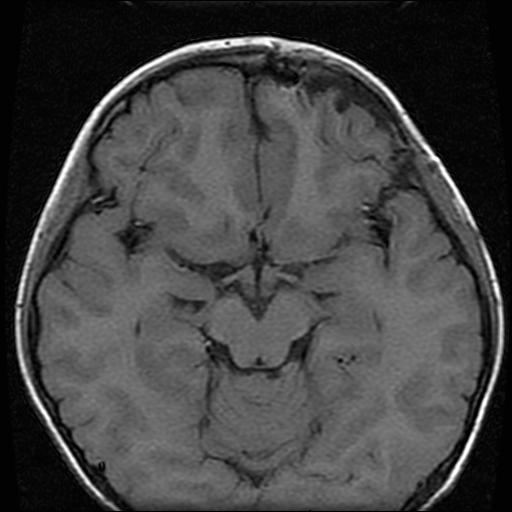

标题: PED0377: 6岁小儿,左侧视神经瘤术后 [打印本页]

6岁小儿,左侧视神经瘤术后。现左侧视力减退。